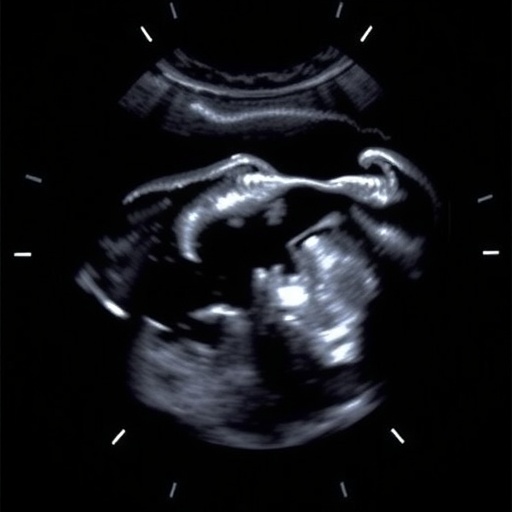

Non-contrast transperineal ultrasound, a technique that involves the application of high-frequency sound waves to visualize internal structures, is gaining traction due to its non-invasive nature and absence of harmful ionizing radiation. Unlike traditional imaging modalities, such as CT scans or contrast-enhanced ultrasounds, this methodology offers a safe alternative for pediatric patients, who are particularly vulnerable to the adverse effects of radiation exposure. The research conducted by Fazecas and colleagues emphasizes the significance of this advancement in the ongoing quest to refine pediatric healthcare.

In their study, the authors meticulously evaluated the efficacy of non-contrast transperineal ultrasound in diagnosing a variety of disorders affecting children. The researchers conducted a comprehensive analysis involving a diverse cohort of pediatric patients, assessing the ultrasound’s ability to accurately detect and characterize different conditions. This analysis highlights the versatility of the ultrasound technique, showcasing its potential in addressing various clinical scenarios effectively.

Moreover, the findings indicate that non-contrast transperineal ultrasound can be particularly advantageous in evaluating children with urogenital disorders and abnormalities. Given that traditional imaging practices often require sedation or invasive procedures in young patients, this ultrasound approach emerges as a favorable alternative that aligns with the principles of pediatric care. It not only reduces the necessity for sedation but also promotes a more comfortable experience for the child and their caregivers.